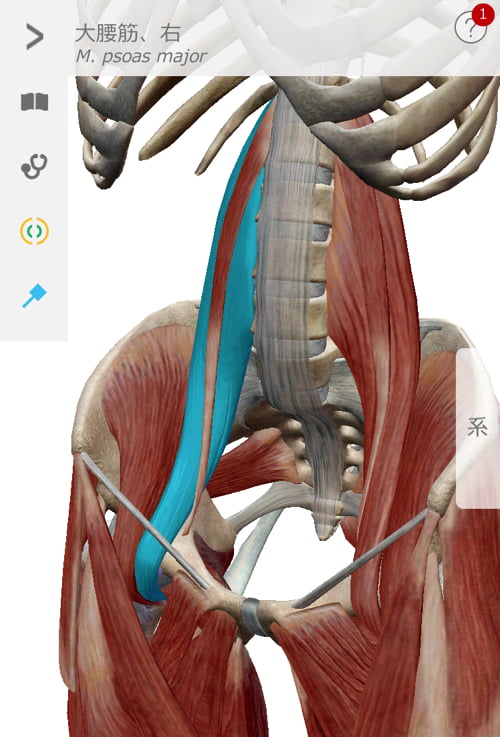

腰ではなく腹筋関連の硬直が大きな原因の1つ

まずはお腹周りから施術して行きます。

ぎっくり腰なのにお腹?と思うかも知れませんが

これらの筋肉が硬直して腰を前に引っ張り出してしまい

腰周りに歪みが出来たりズレが出来たりして痛みが発生するのです。